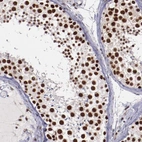

Immunohistochemical staining of human testis shows strong nuclear positivity in cells of seminiferus ducts.